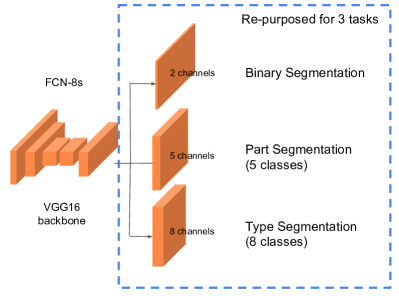

Method 9 was from the University of Alberta (UA). The team consisted of members Zichen (Vincent) Zhang, Xuebin Qin, Min Tang, Shida He, Dana Cobzas and Martin Jagersand. Their method was based on FCN [23] and the overall architecture is illustrated in Fig. 9. It consists of a repurposed FCN-8s for all three tasks. This network architecture was used since it’s relatively smaller than other popular choices such as Resnet-101 [21]. For each video, there are only 1575 (225 7) frames (not considering data augmentation) for training the network. A smaller network would help reduce the risk of overfitting in this setting.

For datasets 1-8, they trained a separate model for each. That is, for each dataset, training was performed using the other seven videos and validation was done on the target video. For dataset 9 and 10, since the entire videos were in the test set, there was no need for excluding any training data. Due to time constraints, they had to reuse the model trained from the dataset 1-8. They ended up picking the model trained for dataset 7 since this dataset contained data that were rarely seen in the other datasets and was perhaps the least useful to train the network on (note that this model was trained on dataset 1-6 and 8). In total, they trained 8 sets of weights for each task, i.e. 24 models in total. The hyperparameters were fixed for all datasets and all tasks. In the binary segmentation task, the network weights were initialized with the pretrained model on PASCAL dataset [23] and fine-tuned on it. The best weights for this task were then used to initialize the network in the part and type segmentation tasks. The input images were resized to 320 256 for faster training.

The network prediction contained some small false positive regions. In post-processing, connected regions smaller than 15000 pixels were removed. This threshold was tuned on the training data.